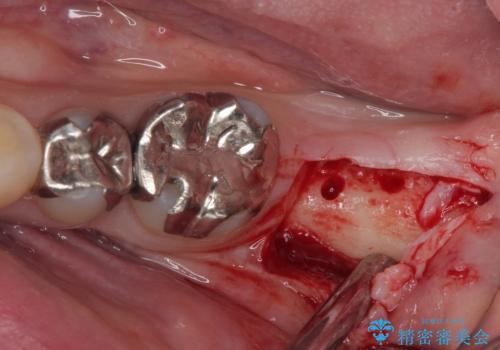

- 奥歯を抜歯してから放置しているとのことで来院された患者様です。

歯が割れて抜歯になってしまったとのことで、咬合力に抵抗できるよう、インプラントによる補綴治療を行うこととしました。

長い期間歯が欠損していた下顎奥歯に、インプラント埋入と同時に仮歯を装着すると(埋入即時荷重インプラントを行うと)、舌の付け根で仮歯を横向きに押してしまい、インプラントが脱落する危険性が高くなります。

インプラント埋入時に、装着できる状態の仮歯を用意するものの、埋入後すぐには加重させず、インプラントが無事に生着したことを確認した後に装着することで、危険を回避しつつ外科処置や痛みの少ないスムーズな治療を行うことができます。